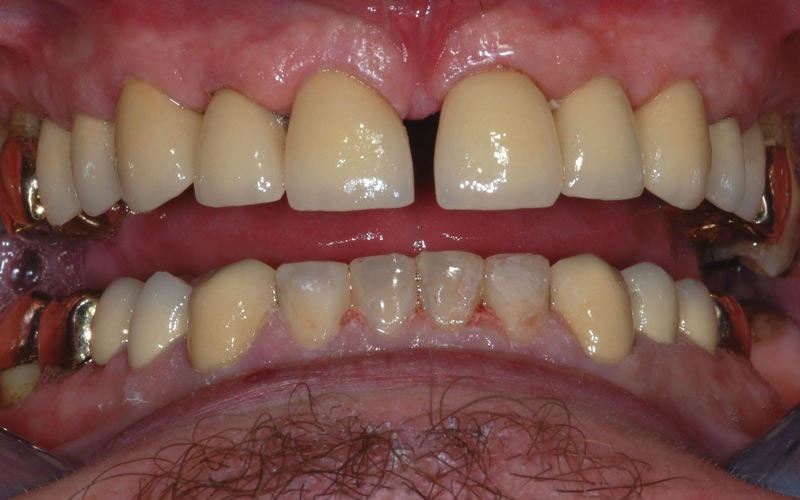

Case Studies

Upper crowns and lower composites (4 images)